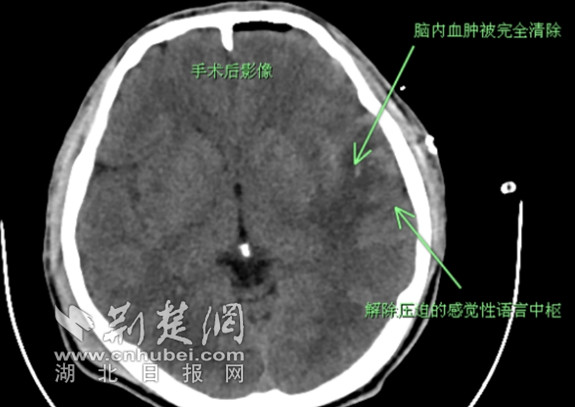

2月21日凌晨,在与患者父母进行充分沟通后,潘德锐主任立即带领医护团队为小余行小骨窗颅内血肿清除术,由于血肿部位离运动功能区非常近,哪怕有多1毫米的损伤都可能留下偏瘫的后遗症,经过一番稳定精细的操作后,手术顺利完成。术后小余被送至ICU过渡并复查CT。当天下午14点,小余便已完全苏醒,语言功能有明显改善,复查CT也提示血肿已完全被清除,2月22日上午,小余成功从ICU转至神经外科普通病房。

复查后脑内血肿已被完全清除 通讯员供图